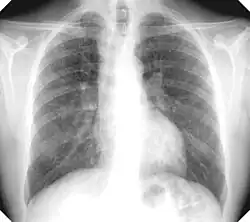

There are three key elements to the diagnosis of silicosis. First, the patient history should reveal exposure to sufficient silica dust to cause this illness. Second, chest imaging (usually chest x-ray) that reveals findings consistent with silicosis. Third, there are no underlying illnesses that are more likely to be causing the abnormalities. Physical examination is usually unremarkable unless there is complicated disease. The examination findings are not specific for silicosis.[20]

For uncomplicated silicosis, chest x-ray will confirm the presence of small (< 10 mm) nodules in the lungs, especially in the upper lung zones. Using the ILO classification system, these are of profusion 1/0 or greater and shape/size "p", "q", or "r". Lung zone involvement and profusion increases with disease progression. In advanced cases of silicosis, large opacity (> 1 cm) occurs from coalescence of small opacities, particularly in the upper lung zones.

With retraction of the lung tissue, there is compensatory emphysema. Enlargement of the hilum is common with chronic and accelerated silicosis. In about 5–10% of cases, the nodes will calcify circumferentially, producing so-called "eggshell" calcification. This finding is not pathognomonic (diagnostic) of silicosis. In some cases, the pulmonary nodules may also become calcified.

Chest X-ray showing uncomplicated silicosis -